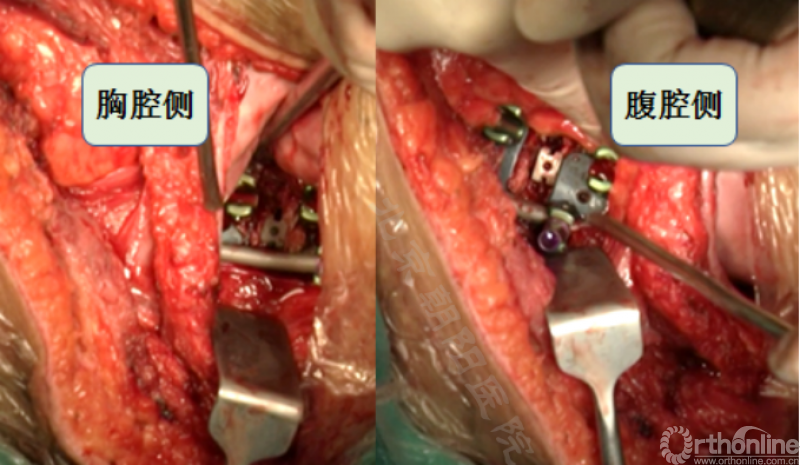

胸腔侧、腹腔侧螺钉全部置入后,骨移植物植人的越靠近后纵韧带或者纤维环的后缘越好。

将预先折弯的金属棒先置入背侧。

椎间融合器经前方置入凹侧,确保腰椎前凸的恢复和冠状面畸形的矫正,将剩下的骨移植物置入椎间隙内。

置入腹侧金属棒。

使用双棒系统时先安装背侧的棒,可进行90°的去旋转,也可以直接通过前方螺钉矫正冠状面和矢状面的畸形,然后固定后方的棒,可进一步通过加压矫正冠状面畸形。

矫正后神经检测未见异常术中唤醒患者下肢活动良好,术中透视矫正效果满意、内固定位置良好。根据手术具体情况放置合适尺寸的横连接加强内固定。